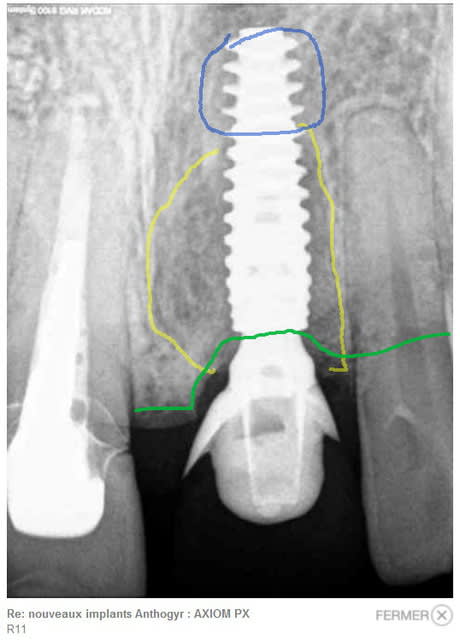

Sur la radio post-op, j'ai dessiné la région où tu aggripes en apical (bleu), la zonne comblée (jaune) et le niveau osseux (vert).

Questions

1-Tu trouves que tu as assez de prise dans l'os pour une MCI ?

2-La zone comblée est large non ?

3-Tu n'as pas un peu trop enfoui l'implant ?

Je suis moins MCI que toi, j'aurais placé plus large, et si possible un bridge collé (pas facile avec le diastème par contre).

> Sur la radio post-op, j'ai dessiné la région où tu aggripes en apical (bleu), la

> zonne comblée (jaune) et le niveau osseux (vert).

>

> Questions

> 1-Tu trouves que tu as assez de prise dans l'os pour une MCI ?

he bien non! enfin... SI !!

> 3-Tu n'as pas un peu trop enfoui l'implant ?

étant donné la destruction osseuse vestibulaire et surtout le niveau du collet des dents proximales (visible sur la radio où on voit la sonde), je pense être à la bonne profondeur.

> étant donné la destruction osseuse vestibulaire et surtout le niveau du collet des dents proximales (visible sur la radio où on voit la sonde), je pense être à la bonne profondeur.

> wait and see!

Si destruction vestibulaire te force à poser plus profond, c'est pa mieux de faire une rog et de ne pas placer trop apical ? Enfin, difficile à voir avec seulement des radio .